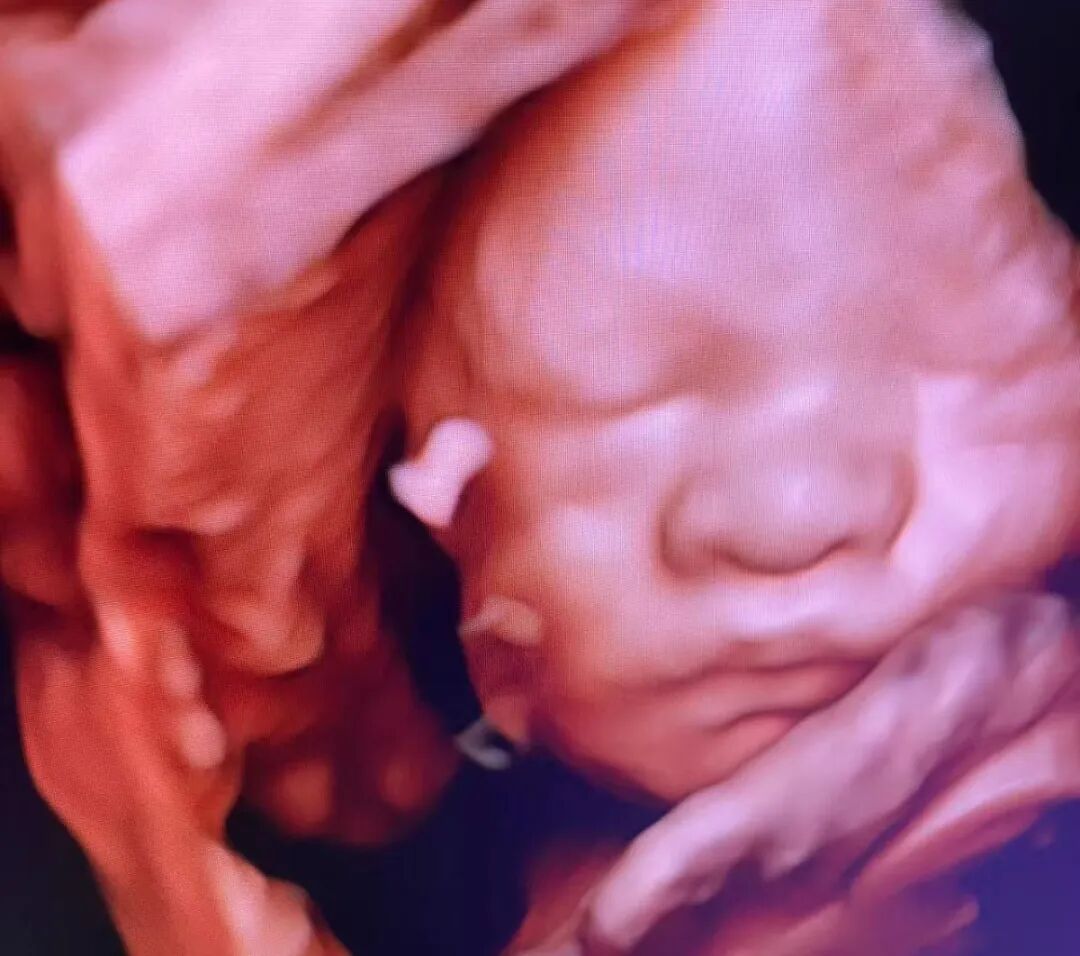

做四维彩超,本是孕期最令人期待的时刻之一——终于可以清晰地看到宝宝的小模样了!小家伙却常“闹小脾气”:睡觉、捂脸、背对镜头...就是不摆“完美pose”。

海南菁华生殖妇产医院B超室的医师们天天和“小调皮”打交道,今天就来给大家支支招,让您和宝宝的第一次“清晰会面”更顺利!

掌握了这些实用小妙招,再配合海南菁华生殖妇产医院B超室医师们的专业护航,让宝宝“配合”不再难!经验丰富的他们深谙与“小调皮”的周旋之道,操作准确轻柔,还会特别预留充足时间,运用先进设备,清晰捕捉宝宝每一帧珍贵影像,守护您与宝宝的清晰初见!